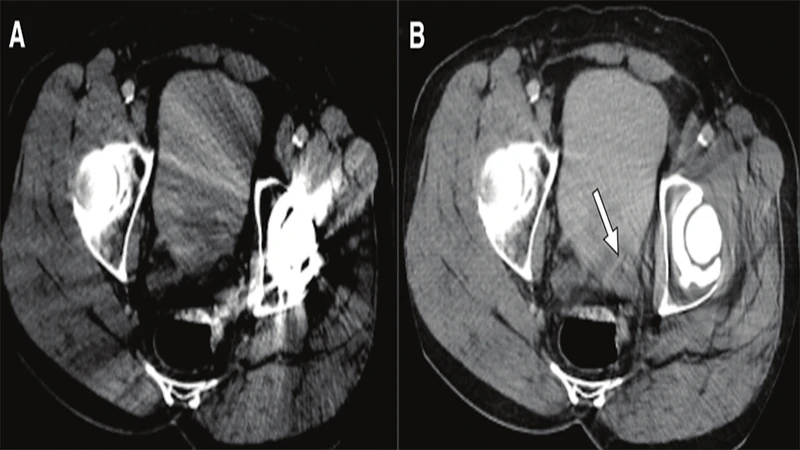

2. Metal Artifact

Metal objects on or inside the patient can severely distort the image, particularly in CT and MRI.

- Appearance (CT): Severe streaking or "starburst" patterns originating from the metal object.

- Appearance (MRI): Large, dark signal voids with bright, distorted edges. The distortion is often much larger than the object itself.

- Cause: High-density metal (like dental fillings, surgical clips, or joint replacements) completely absorbs X-rays in CT. In MRI, ferromagnetic metals distort the local magnetic field.